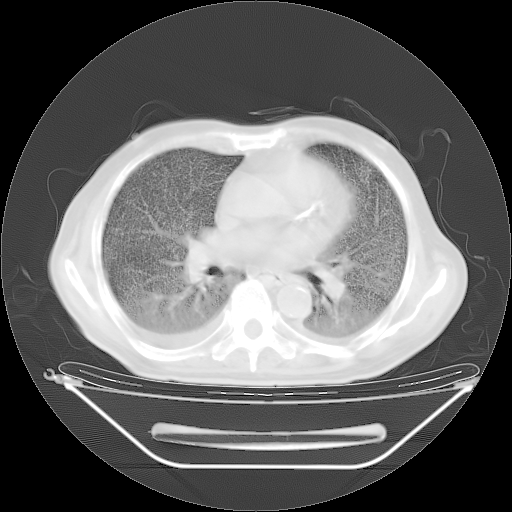

今天复查肺部CT,发现双肺广泛磨玻璃样改变。所以我把3月19日和5月9日相隔50天的肺部CT上传。请大家会诊。

2009年3月19日肺部CT片。

2009年3月19日肺部CT

5月9日肺部CT(在4月27日齐鲁医院肺部CT描述部分肺组织磨玻璃样改变,12天后肺组织广泛磨玻璃样改变)